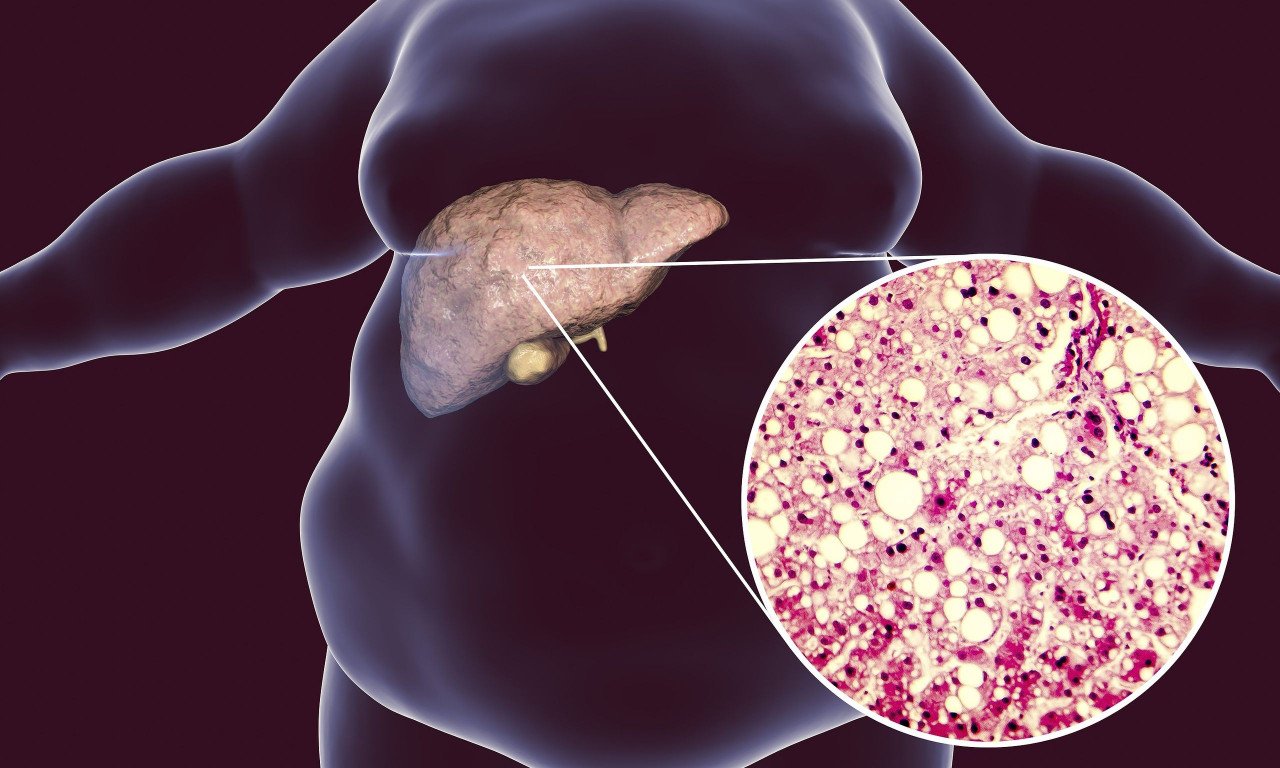

Η πάθηση επηρεάζει σχεδόν το ένα τρίτο του παγκόσμιου πληθυσμού, εξελίσσεται αθόρυβα και είναι στενά συνδεδεμένη με διαδεδομένα προβλήματα υγείας, όπως η παχυσαρκία και ο διαβήτης τύπου 2.

Λόγω του επιπολασμού και των ισχυρών συνδέσεων με άλλες καρδιομεταβολικές παθήσεις, η μεταβολικά σχετιζόμενη στεατωτική νόσος του ήπατος αποτελεί σημαντική πρόκληση για την παγκόσμια υγεία.

Η μεταβολικά σχετιζόμενη στεατωτική νόσος του ήπατος είναι μια σύνθετη πάθηση που οφείλεται σε ένα συνδυασμό γενετικών, περιβαλλοντικών και συμπεριφορικών παραγόντων.

Η διάγνωση εξαρτάται από την παρουσία ηπατικής στεάτωσης μαζί με τουλάχιστον έναν καρδιομεταβολικό παράγοντα κινδύνου, όπως παχυσαρκία, δυσλιπιδαιμία, αντίσταση στην ινσουλίνη ή διαβήτη τύπου 2.

Οι ασθενείς συχνά παρουσιάζουν μια σειρά κλινικών παραμέτρων, όπως μεταβολές στον δείκτη μάζας σώματος (BMI), αυξημένη περίμετρο μέσης, διαταραχή του μεταβολισμού της γλυκόζης (αυξημένη γλυκόζη νηστείας και αντίσταση στην ινσουλίνη), κακό λιπιδαιμικό προφίλ και αυξημένους δείκτες φλεγμονής.

Αυτές οι μεταβολικές διαταραχές υπογραμμίζουν την ανάγκη ολιστικών προσεγγίσεων που αντιμετωπίζουν όχι μόνο την υγεία του ήπατος, αλλά και τη συνολική μεταβολική υγεία.

Η πάθηση επηρεάζει σχεδόν το ένα τρίτο του παγκόσμιου πληθυσμού, εξελίσσεται αθόρυβα και είναι στενά συνδεδεμένη με διαδεδομένα προβλήματα υγείας, όπως η παχυσαρκία και ο διαβήτης τύπου 2.

Λόγω του επιπολασμού και των ισχυρών συνδέσεων με άλλες καρδιομεταβολικές παθήσεις, η μεταβολικά σχετιζόμενη στεατωτική νόσος του ήπατος αποτελεί σημαντική πρόκληση για την παγκόσμια υγεία.

Η μεταβολικά σχετιζόμενη στεατωτική νόσος του ήπατος είναι μια σύνθετη πάθηση που οφείλεται σε ένα συνδυασμό γενετικών, περιβαλλοντικών και συμπεριφορικών παραγόντων.

Η διάγνωση εξαρτάται από την παρουσία ηπατικής στεάτωσης μαζί με τουλάχιστον έναν καρδιομεταβολικό παράγοντα κινδύνου, όπως παχυσαρκία, δυσλιπιδαιμία, αντίσταση στην ινσουλίνη ή διαβήτη τύπου 2.

Οι ασθενείς συχνά παρουσιάζουν μια σειρά κλινικών παραμέτρων, όπως μεταβολές στον δείκτη μάζας σώματος (BMI), αυξημένη περίμετρο μέσης, διαταραχή του μεταβολισμού της γλυκόζης (αυξημένη γλυκόζη νηστείας και αντίσταση στην ινσουλίνη), κακό λιπιδαιμικό προφίλ και αυξημένους δείκτες φλεγμονής.

Αυτές οι μεταβολικές διαταραχές υπογραμμίζουν την ανάγκη ολιστικών προσεγγίσεων που αντιμετωπίζουν όχι μόνο την υγεία του ήπατος, αλλά και τη συνολική μεταβολική υγεία.